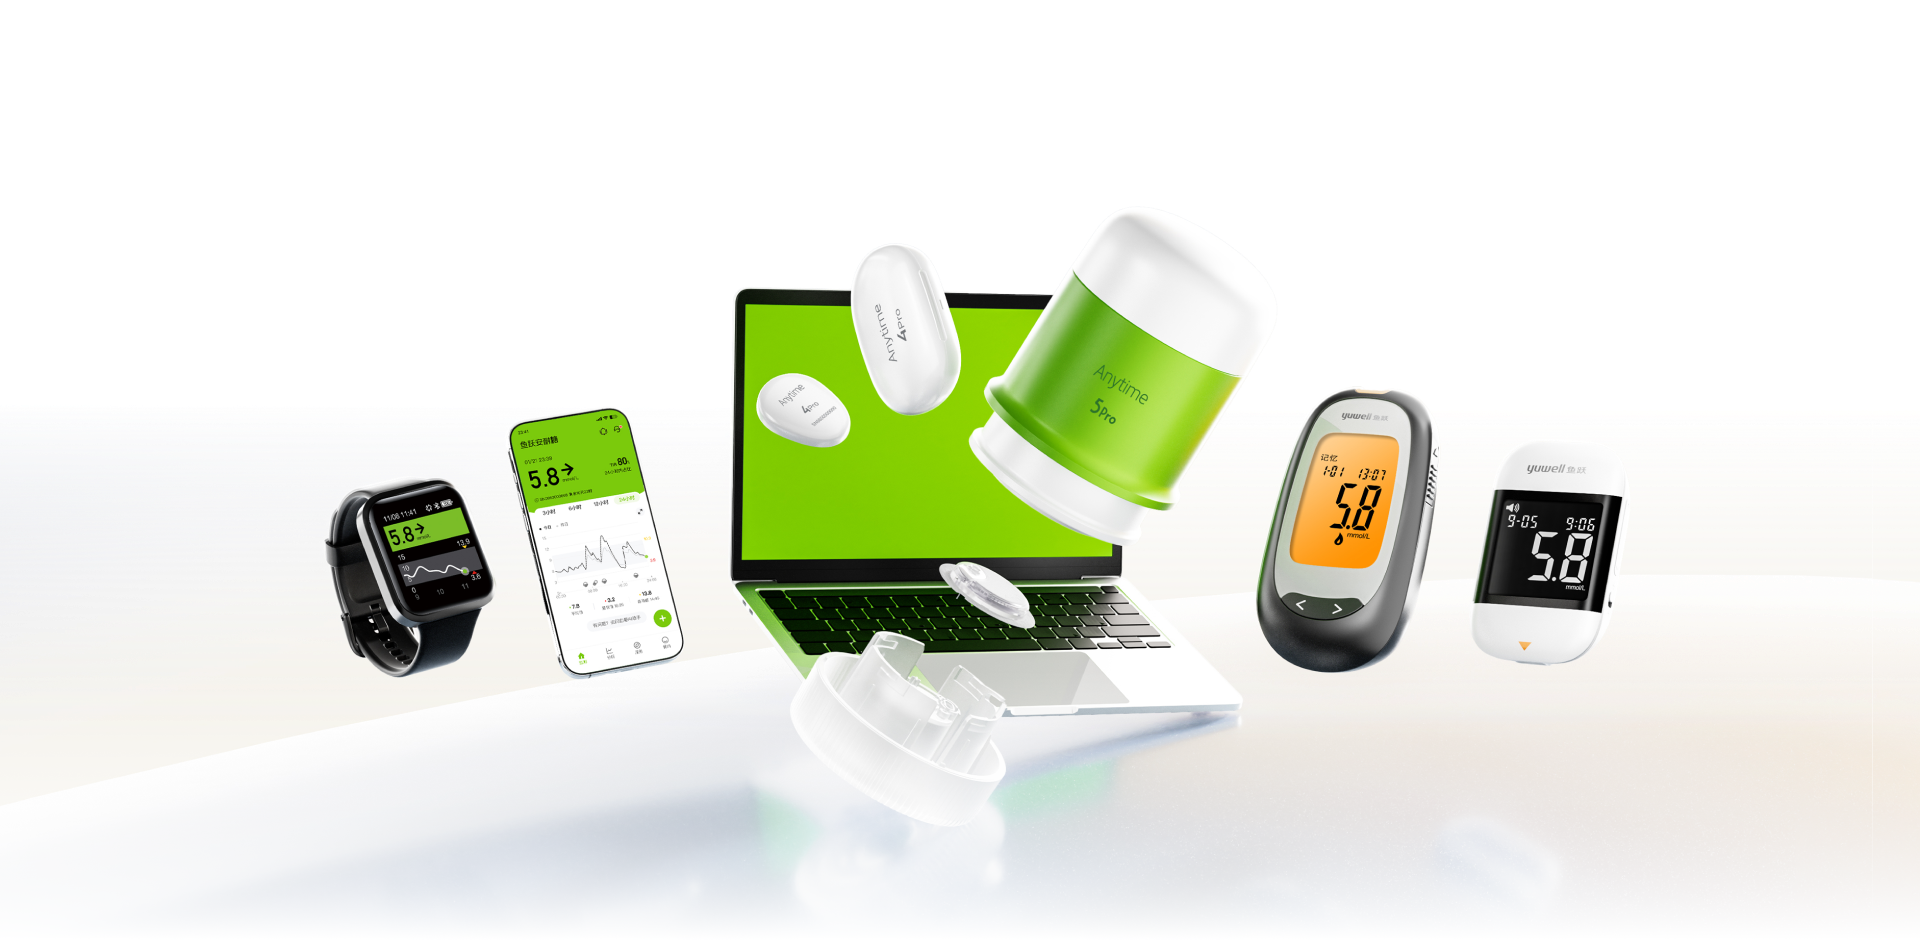

关于鱼跃凯立特

鱼跃凯立特是鱼跃集团下专注于血糖及相关指标监测产品的子公司,集研发、生产与销售于一身,致力于不断用创新向全球100余个国家提供生物传感、电化学、免疫层析产品。

我们的服务方案

个人居家监测方案

专业医疗机构方案

连锁药房方案

数字化方案

陪伴·连接·专注

我们的血糖监测解决方案,持续为全球超100+国家与地区的医院与用户服务